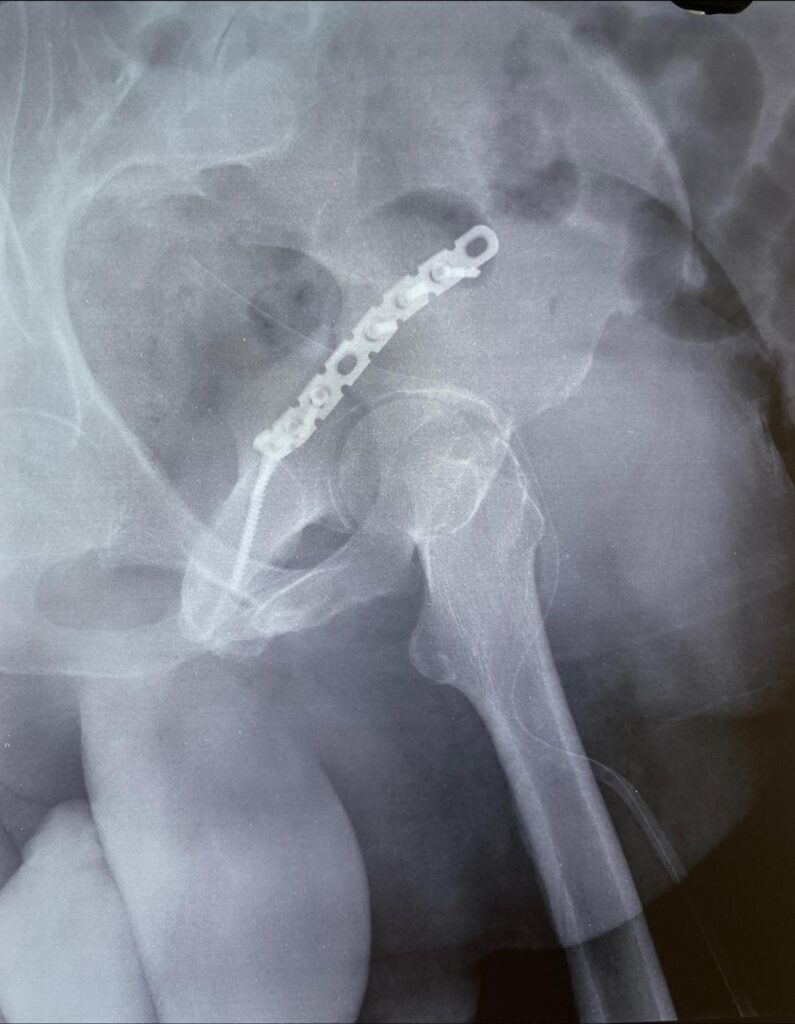

Neck of Femur Fractures

Most neck of femur fractures are treated with partial or total jointreplacement surgeries. however doing so limits active lifestyle in younger individuals. Especially in the Indian system of living. that is why it’s important to take such fractures as surgical emergencies in young people like this 43 year old woman and treat them with screw […]